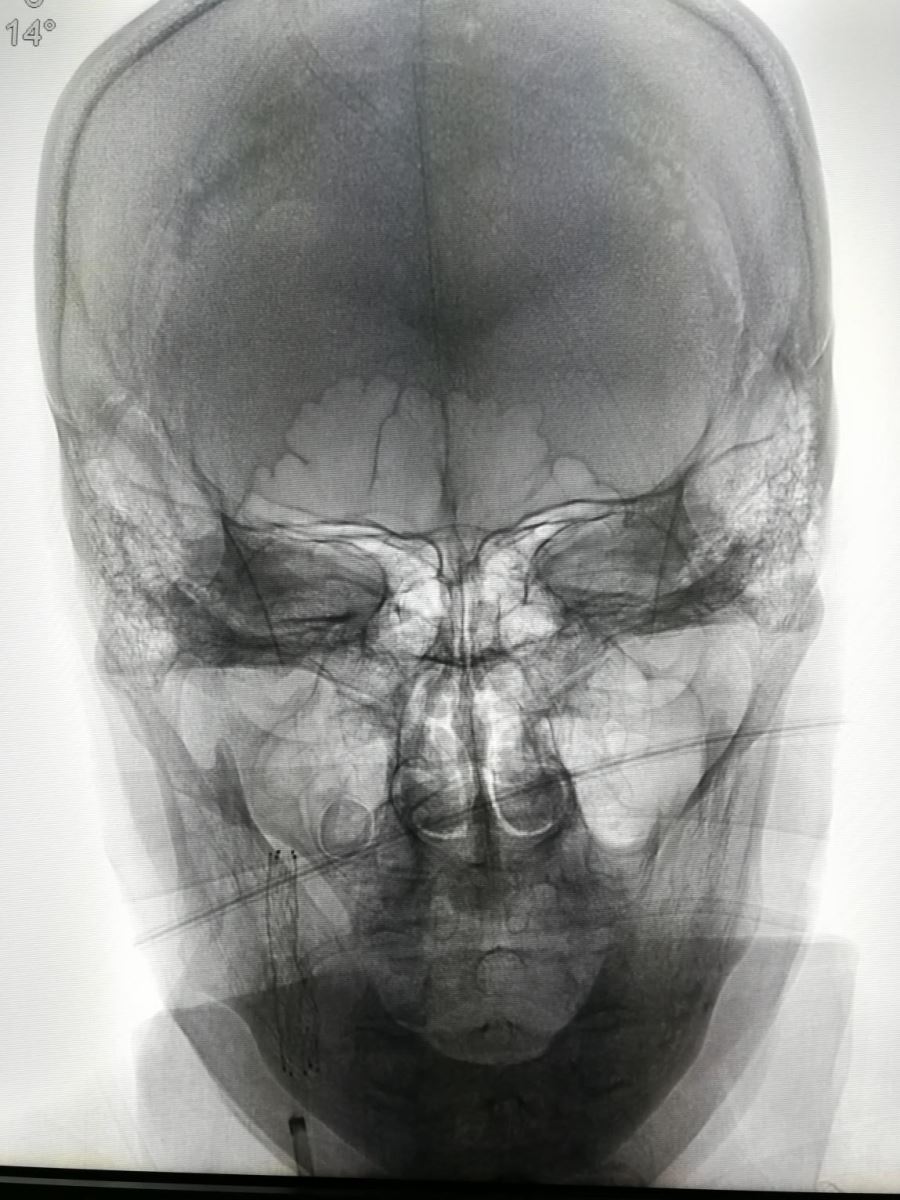

头颅CT、头颅MRI、MRA(磁共振颅内动脉血管成像)已广泛应用于临床,对脑血管病的定位、定性诊断帮助极大,但是并不是所有脑梗死患者的病变原因都在颅内。缺血性卒中发病原因的Toast分型,第一项即为大动脉粥样硬化性病变引起的卒中,因此应引起重视。如图1:

图1

如果单看颅内血管成像,无需介入治疗,但如果连同颈部动脉血管成像(图2、3)。